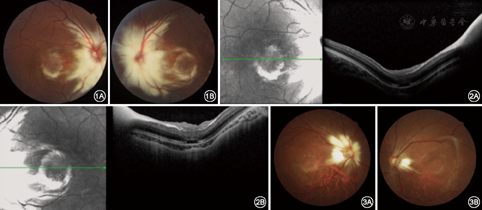

患儿男性,3岁。父母发现患儿自幼双眼视力差,于2017年3月14日就诊于复旦大学附属眼耳鼻喉科医院眼科。全身体检:未见明显异常。眼部检查:最佳矫正视力右眼为0.1(-6.00 D),左眼为0.08(-6.50 D);双眼外眼及前节未见明显异常;双眼视盘周围白色斑块,边缘呈羽毛状,病灶沿神经纤维分布;双眼黄斑部亦可见白色羽毛样改变(图1);OCT检查:双眼后极部神经纤维层呈高反射信号,神经纤维层前可见中低信号物质,可能为视网膜前胶质增生或玻璃体后皮质异常堆积(图2)。临床诊断:双眼RMNF。对患儿的父母进行检查,发现其母亲双眼视盘周围也有白色斑块,呈羽毛状分布,双眼视盘发育不良,高度近视眼样改变(图3)。患儿及其母亲均未给予特殊治疗,定期随访观察。

RMNF最好发于视盘上方且多无症状[1],而位于黄斑区的病灶则会导致严重的视力损伤,甚至出现畏光等临床症状[7]。由于存在形觉剥夺,故RMNF分布在视轴区的患者可发生严重的轴性近视眼[8],且有髓神经纤维的分布范围与近视程度呈正相关[9]。本文患儿病灶广泛并累及黄斑区,后极部出现豹纹状改变并形成葡萄肿,OCT图像显示脉络膜显著变薄。患儿的母亲双眼视盘发育不良,眼底豹纹状改变,视盘旁萎缩弧形成。

绝大多数RMNF患者的眼底改变常为独立的眼部体征,但也可合并其他眼部异常,如RMNF病灶处并发视网膜血管异常[10,11]、黄斑前膜[12]、玻璃体黄斑牵引[13]、视网膜裂孔[14]等。本文患儿OCT图像显示在黄斑前有一层较厚的中低反射信号,推测可能为黄斑前胶质增生或玻璃体后皮质异常堆积。